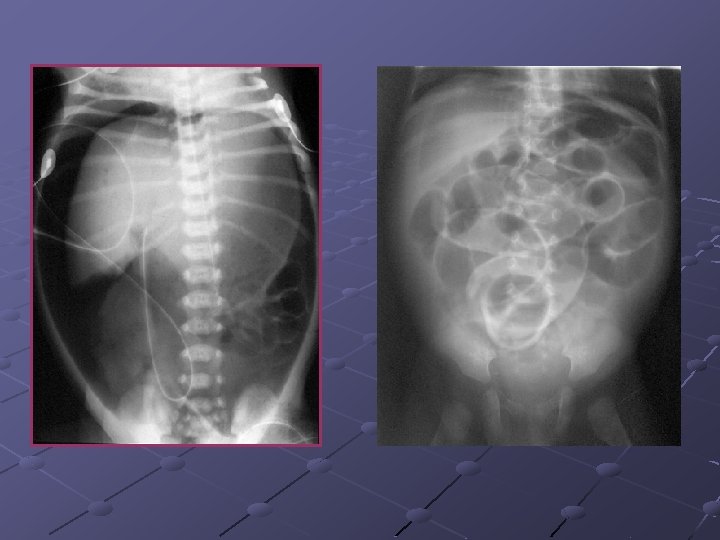

CAS N° 2 Absence d’émission du méconium Ballonnement depuis J 0 Bilan radiologique de J 2

Atrésie du grêle Interruption de la continuité intestinale Siège: duodénum (50%), jéjunum (35%) et iléon (15%) Facteurs fav évoqués: RCIU, consng. Infection maternelle, prise de cocaïne chez la femme enceinte… Prévalence: 0, 4 -2, 3 pour 10 000 Nces Théorie acceptée de nos jours: ischémie intestinale intra-utérine avec nécrose et résorption du segment concerné -thromboembolie -hypoxie fœtale -volvulus I-U -hernie interne -invagination intestinale aiguë